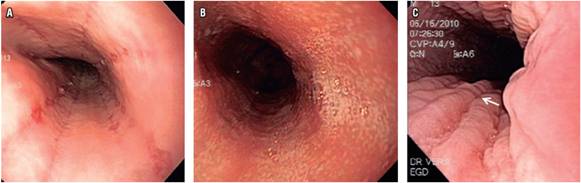

Los hallazgos endoscópicos esofágicos más frecuente-mente encontrados fueron los exudados blanquecinos, con 16 casos (34,78 %), y los surcos longitudinales encontrados en 7 casos (15,21 %) (Figura 1). Considerando los antecedentes de síntomas digestivos asociados con enfermedad atópica, así como los hallazgos endoscópicos, en 23 pacientes se sospechó EEo (50 %), en 14 pacientes (30,43 %) se consideró esofagitis erosiva péptica y en 2 pacientes (4,34 %) se sospechó esofagitis por Cándida spp (Tabla 2).

Con respecto a los hallazgos endoscópicos, las alteraciones más frecuentemente encontradas en esta serie fueron los exudados blanquecinos y los surcos longitudinales. Solamente en la mitad de los pacientes, considerando los hallazgos endoscópicos y las características clínicas, el especialista consideró a la EEo como diagnóstico endoscópico principal, lo cual demuestra la importancia de toma de biopsias.